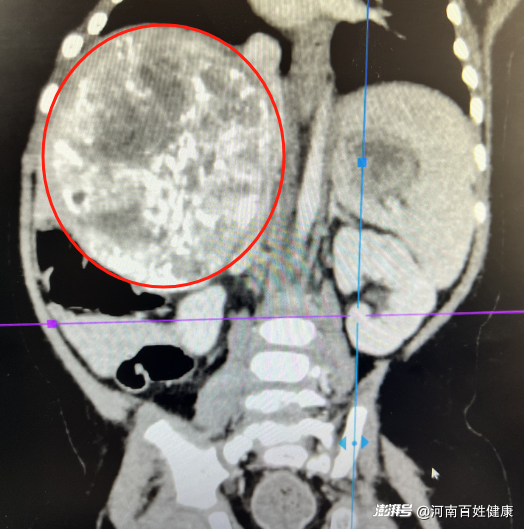

一個100*114*107mm(前后*左右*上下)巨大的肝母細(xì)胞瘤已經(jīng)占據(jù)了團(tuán)團(tuán)小小的肝臟,并緊貼肝中靜脈及下腔靜脈,因腫瘤體積過大且位置特殊,當(dāng)?shù)蒯t(yī)院建議轉(zhuǎn)至上級醫(yī)院治療。

經(jīng)過專家們討論,建議患兒先進(jìn)行化療,待腫瘤控制后再進(jìn)行切除。終于,經(jīng)過4次化療后,團(tuán)團(tuán)復(fù)查CT顯示腫瘤較前有所縮小,具備了接受肝腫瘤切除手術(shù)的條件。

隨著安全顯影劑注入患兒體內(nèi),這個藏在肝右葉及尾葉、侵犯肝中靜脈及下腔靜脈的腫瘤被勾勒出來。由于腫瘤體積較大、且與周圍組織緊密粘連,邊界不清,手術(shù)團(tuán)隊既要徹底切除腫瘤,又要最大限度保護(hù)肝臟及功能,同時精準(zhǔn)控制出血。